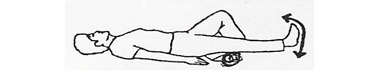

به پشت دراز بکشید، پا را خم و راست کنید. این حرکت را 10 بار تکرار کنید. بروز اندکی درد در ابتدای این تمرین طبیعی است، اما حتماً مطمئن شوید که آسیبی به جراحت زانو وارد نمیشود.

عضلههای باسن را محکم به یکدیگر فشار دهید. 5 ثانیه در این حالت بمانید، سپس 5 ثانیه استراحت کنید و عضلهها را شل کنید. این حرکت را 10 بار تکرار کنید. این تمرین نیز از تشکیل لختههای خون جلوگیری میکند. این حرکت را در زمان بیداری هر یک ساعت یکبار انجام دهید.